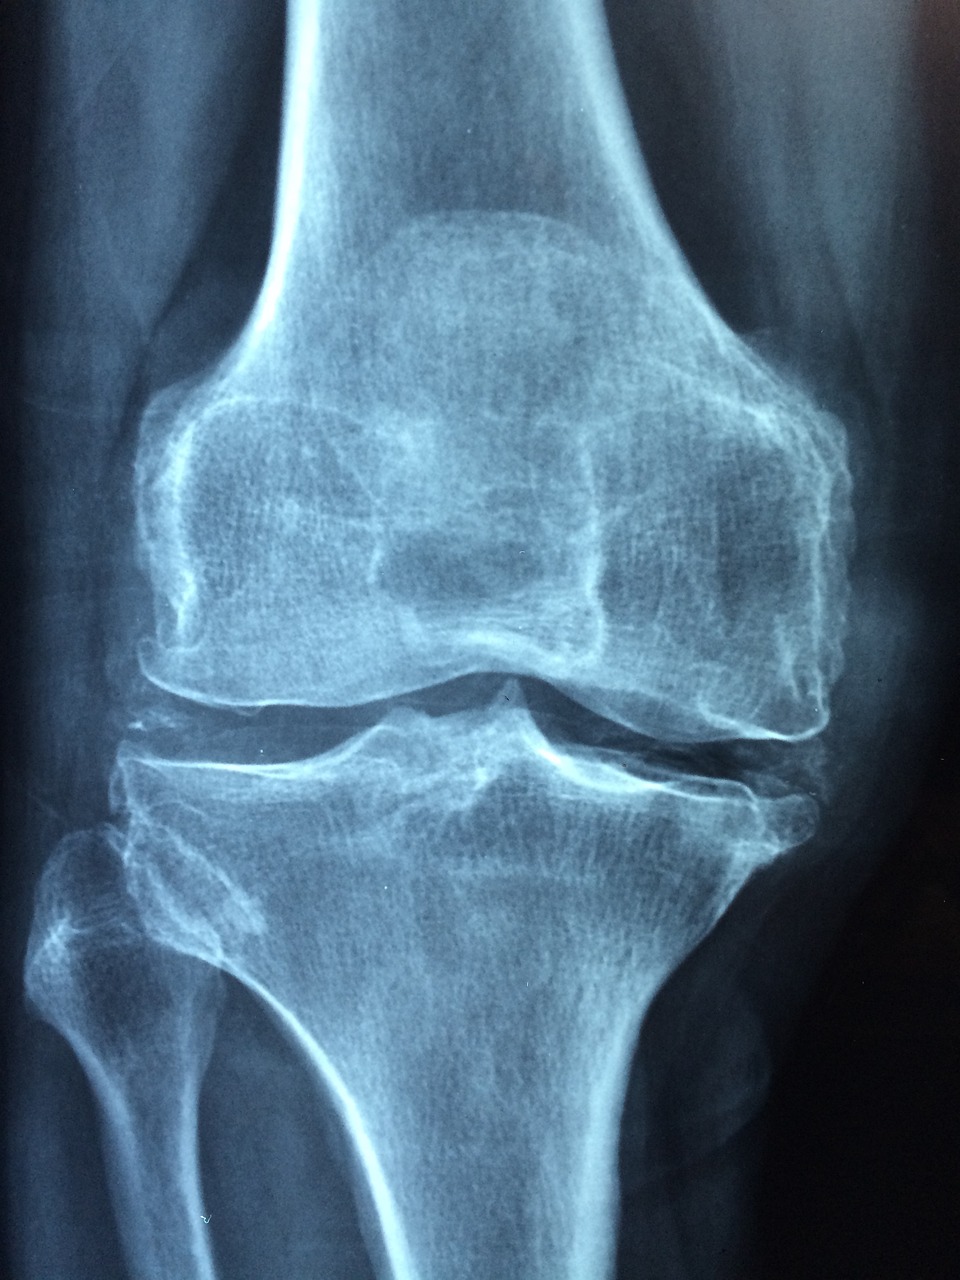

A osteoporose é uma condição silenciosa, que só é detectada por exames de densitometria óssea ou após fraturas, como explica Elaine de Azevedo, da Sociedade Brasileira de Reumatologia. O diagnóstico é muitas vezes tardio, e cerca de 80% das pessoas que sofrem fraturas causadas pela fragilidade óssea não recebem o diagnóstico correto.